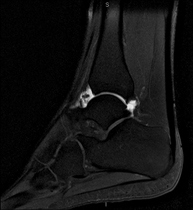

- Ankle MRI

Examination to study the joint and its frequent ligament injuries (sprains) as well as damage to other structures such as cartilage or bone. It is also very useful for diagnosing disorders of the Achilles tendon (tendinitis, ruptures). Duration: approximately 20 minutes. It is a radiation-free procedure.

- Ankle MRI arthrography

Examination to study injuries to small anatomical structures of the joint that are commonly injured in patients suffering from dislocation or chronic instability. Prior to the examination, a contrast fluid is injected into the joint, guided by X-ray imaging. The total duration of the two procedures is 50 minutes.